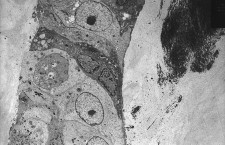

Последние исследования подтверждают, что аборты повышают риск развития рака груди

По данным специалистов из Коалиции по борьбе с абортами и раком груди, в 53 из 69 эпидемиологических исследований, проведённых за 1957-2013 гг., учёные обнаружили повышение риска развития рака груди у женщин с абортом в анамнезе